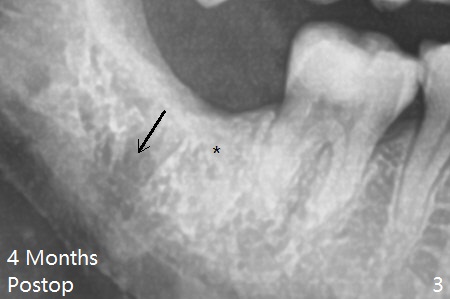

With incision, buccal trough is created at #32 for elevators so that the 2nd molar is not affected by elevation.  Collagen plug is placed in the socket to prevent dry socket (Fig.2).  The mesial socket is completely ossified (Fig.3 *), while the distal one partially ossified 4 months postop.  The ossification in the distal socket seems to be from coronal to apical (Fig.3 arrow), in contrast to the traditional thinking of apico-coronal.  The corono-apical growth may be related to Collagen plug placement.  The plug is probably not originally inserted into the distal apical region.